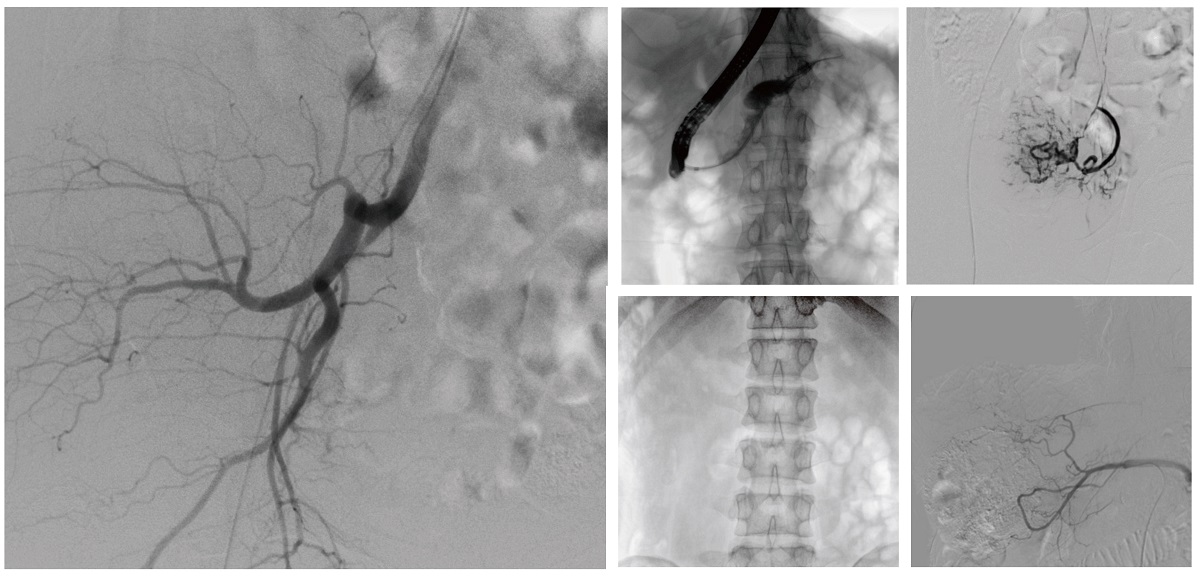

醫(yī)院引進(jìn)的普愛(ài)醫(yī)療移動(dòng)式平板介入中C,其高清成像能力覆蓋骨科、介入科、泌尿外科、婦產(chǎn)科等多科室,能夠滿足介入微創(chuàng)手術(shù)的多樣化需求。

設(shè)備的移動(dòng)式設(shè)計(jì),無(wú)需對(duì)現(xiàn)有手術(shù)室進(jìn)行改造,適合高負(fù)荷手術(shù)量或應(yīng)急情況下的靈活部署。如在急診介入手術(shù)中,該設(shè)備能迅速響應(yīng)需求,為醫(yī)生提供實(shí)時(shí)影像支持,提升搶救效率。